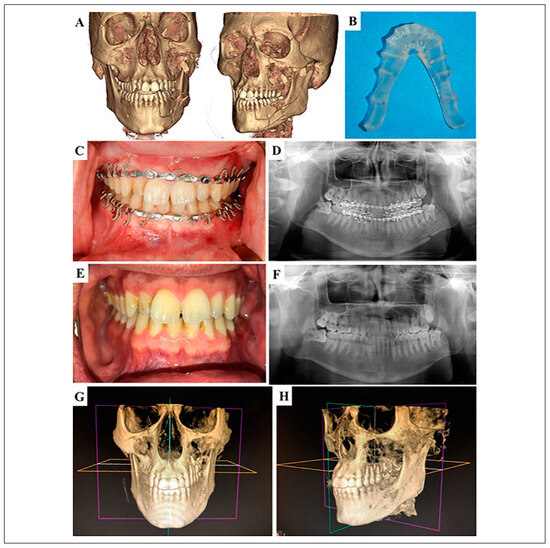

Utilization of Virtual Surgical Planning for Surgical Splint-Assisted Comminuted Maxillomandibular Fracture Reduction and/or Fixation

Data Acquisition and Presurgical Planning

Surgical Procedure

Results